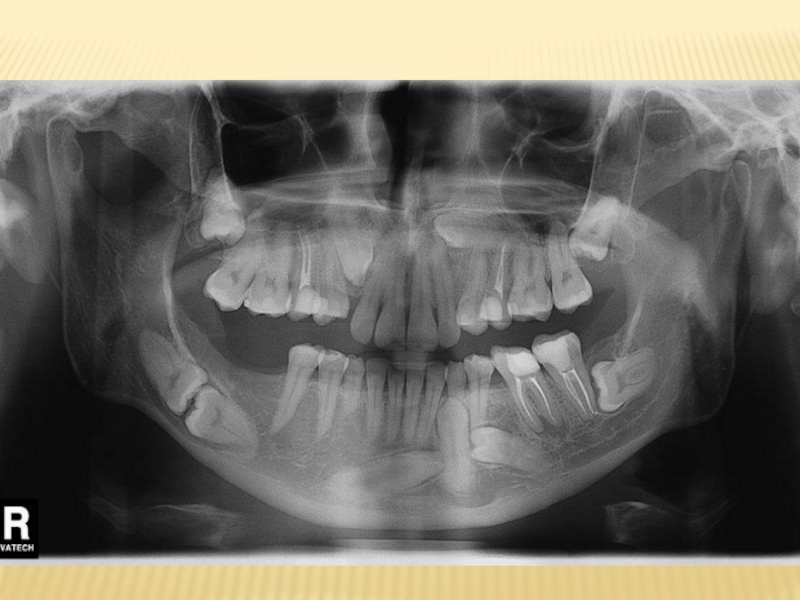

Для постановки диагноза и составления плана лечения используются следующие лучевые

методы исследования:

1) дентальная рентгенография

2) боковая рентгенография нижней челюсти

со стороны локализации патологического процесса;

3) ортопантомография

4) спиральная компьютерная томография;

5) конусно-лучевая компьютерная томография

Наиболее часто в практическом здравоохранении используются ден-тальная рентгенография и ортопантомография, однако оптимальными ме-тодами исследования при болезнях прорезывания являются ортопантомо-графия и конусно-лучевая компьютерная томография коническим пучком .

Эффективные дозы облучения при различных методах лучевой диагностики заболеваний челюстно-лицевой области следующие:

‒ при дентальной рентгенографии — 0,01–0,02;

‒ ортопантомографии — 0,07–0,15;

‒ спиральной компьютерной томографии с 3D-реконструкцией — 1,2–2,3;

‒ конусно-лучевой компьютерной томографии — 0,036